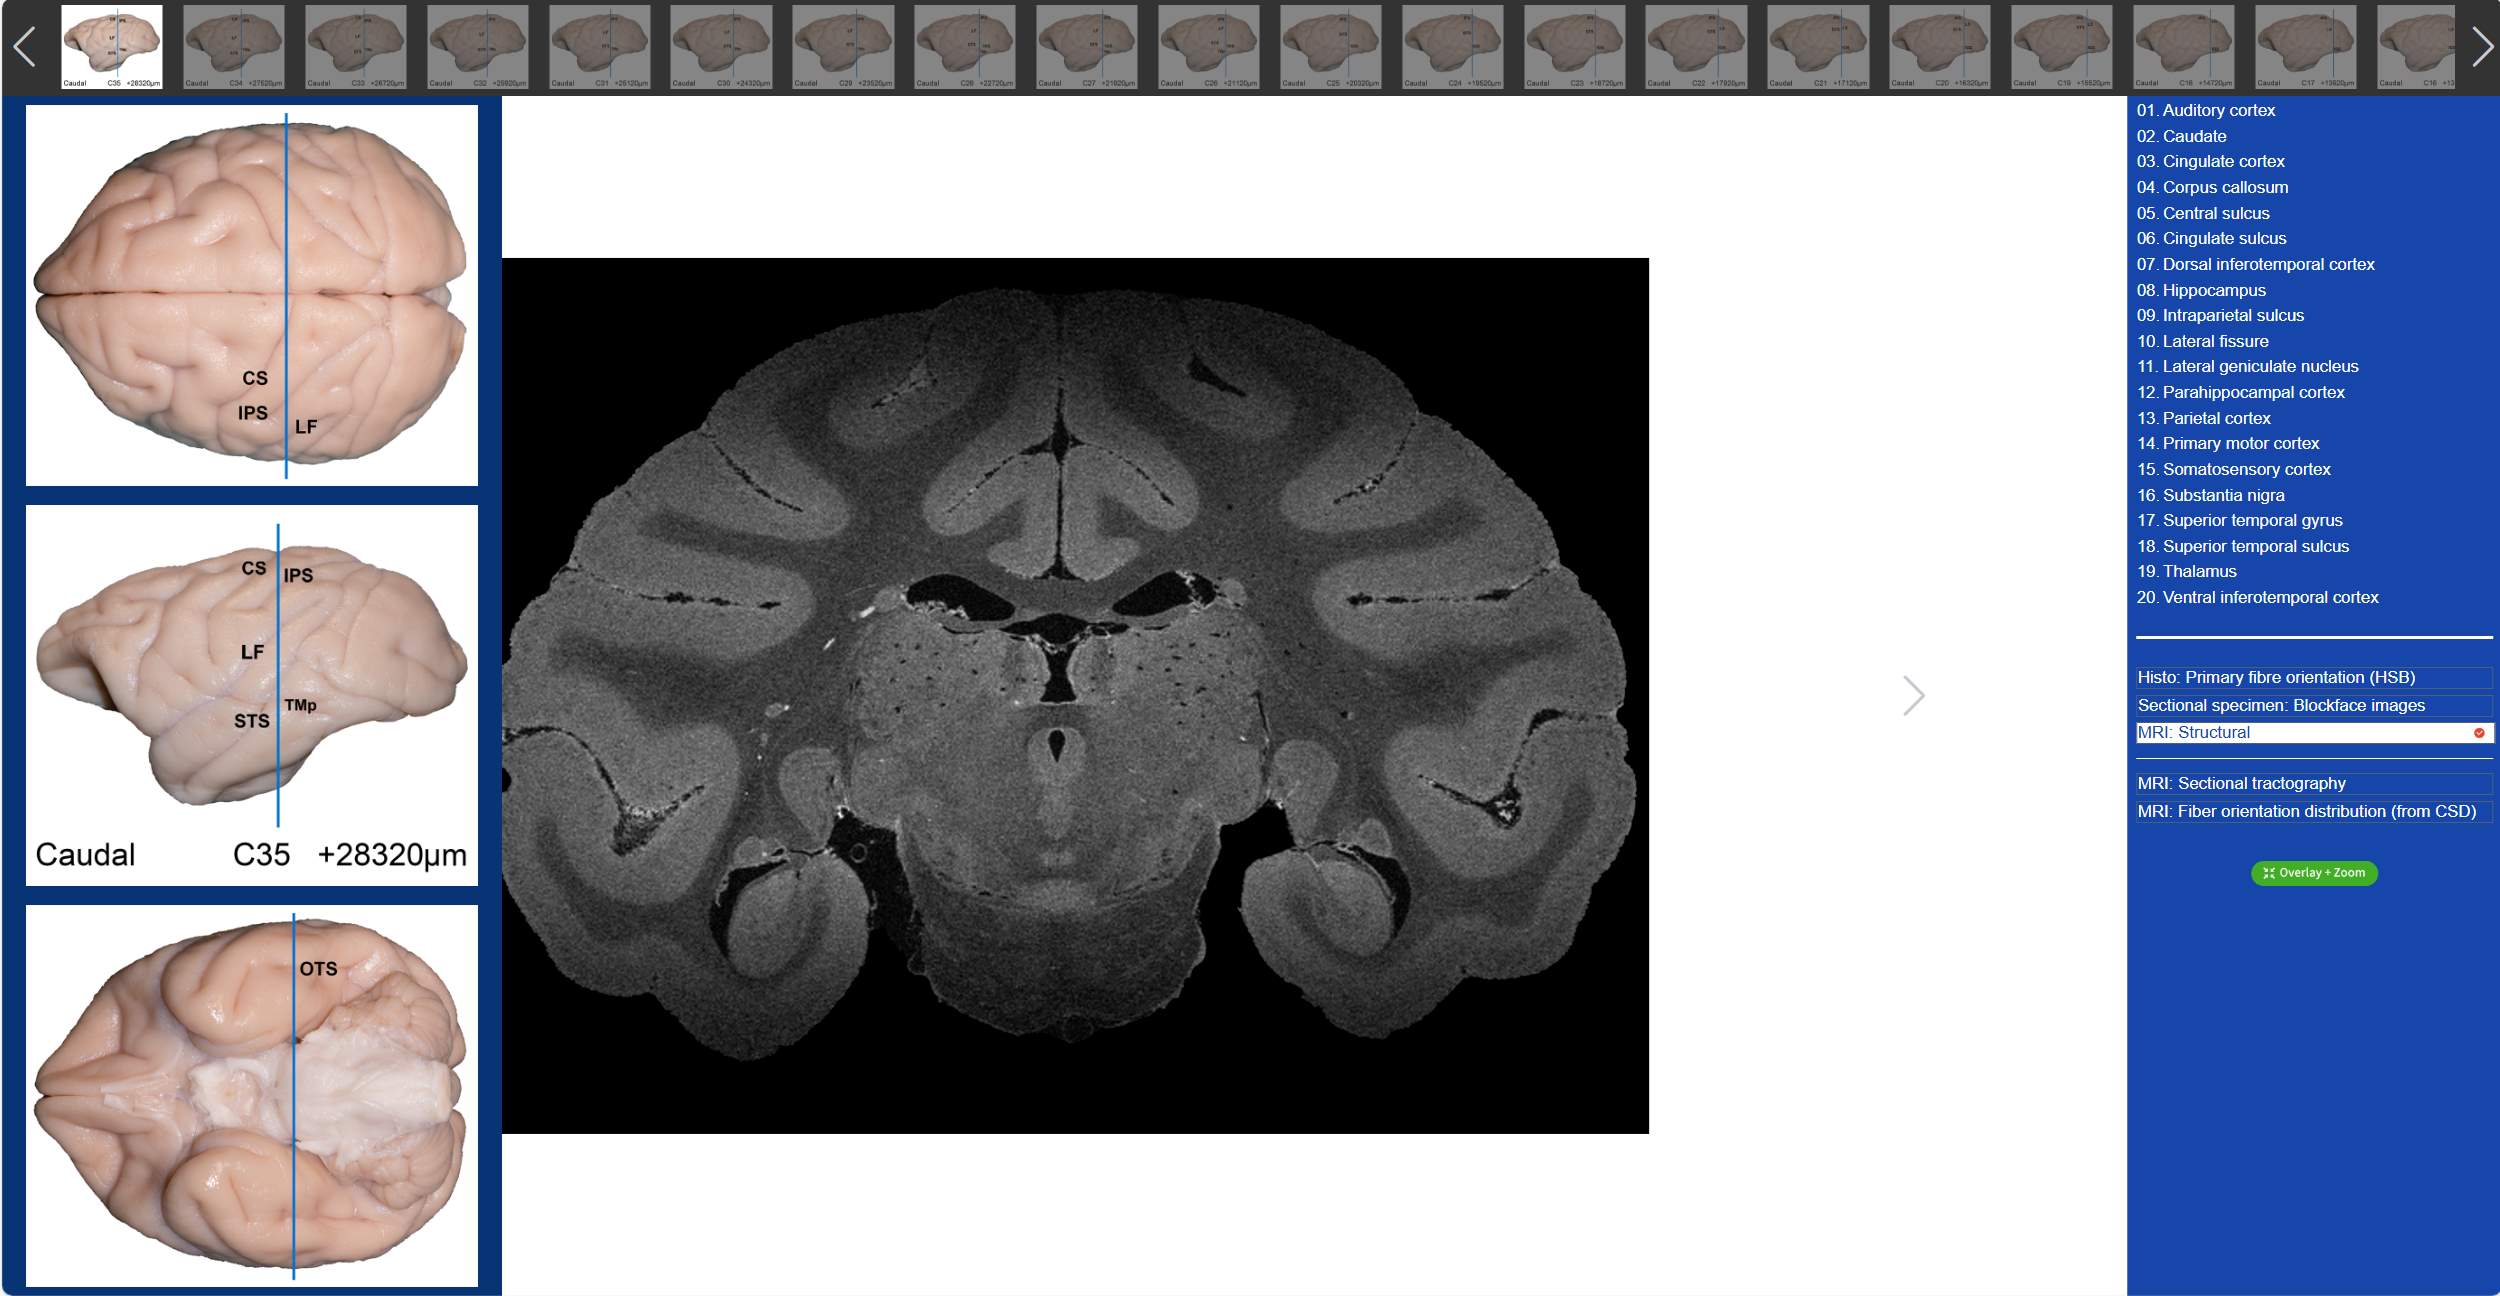

值得一提的是,在“動物腦樂園”里,不僅可以觀察到獼猴3D腦標本,還可以看到獼猴的全腦切片。吳勁松教授團隊從同一猴腦的離體MRI及全腦組織切片髓鞘染色(LFB)數據集中,間隔800μm取一層,構建了集合組織切片髓鞘染色(LFB)、組織切片髓鞘染色-偽彩化、斷層標本圖、高分辨率MRI結構像及離體腦dMRI斷層纖維束成像和纖維方向分布圖(限制球面反卷積-CSD)六大模態的斷層對照圖譜。我們只需要點擊相應的解剖名稱,就可以在圖譜上對應位置顯示標記,同時可與另外兩大模態的dMRI方向性信息進行對照,極大的方便了我們的觀看。